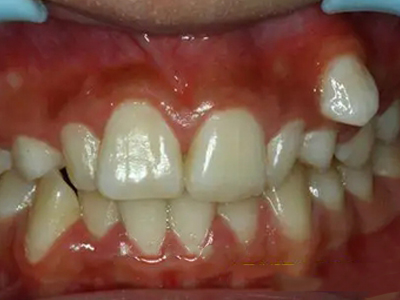

阻生牙是指由于邻牙、骨或软组织的阻碍而只能部分萌出或完全不能萌出,且以后也不能萌出的牙。引起牙阻生的成因,主要是由于颌骨缺乏足够的空间容纳全部恒牙。常见的阻生牙为下颌第三磨牙、上颌第三磨牙及上颌尖牙。

阻生牙可反复引起冠周炎,或引起邻牙牙根吸收和破坏,位置不正,不能完全萌出,好发部位是上、下颌第三磨牙。